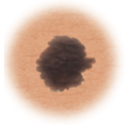

Color

When the color of the mole varies throughout